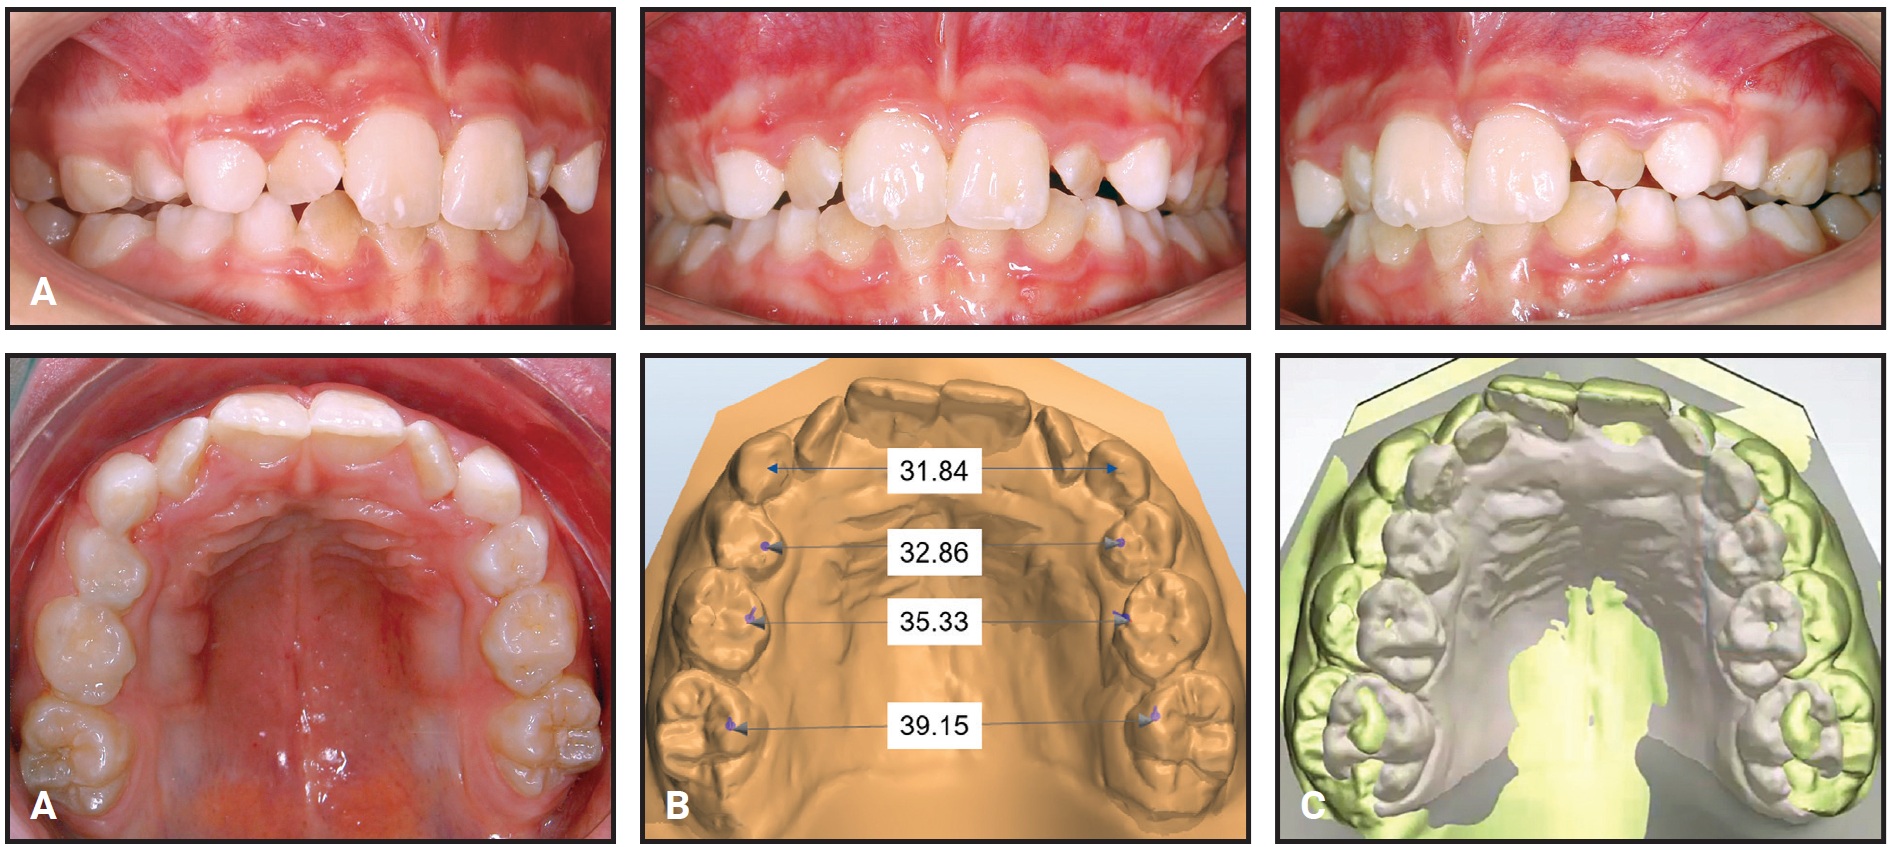

Fig. 5 Case 1. A. Self Expander removed after five months of passive retention. B. Arch-width measurements on STL digital cast. C. Superimposition of pre- and post-treatment scans on palatal rugae.

The patient was checked six times during seven months of active expansion, and the Self Expander was then left in place for three months of retention. The crossbite was corrected, the maxilla was expanded enough to allow eruption of the permanent lateral incisors, and the first permanent molars showed spontaneous expansion and derotation, guided by the occlusion (Fig. 9).

Fig. 9 Case 2 A. Self Expander removed after three months of passive retention. B. Arch-width measurements on STL digital cast. C. Superimposition of pre- and post-treatment scans on palatal rugae.